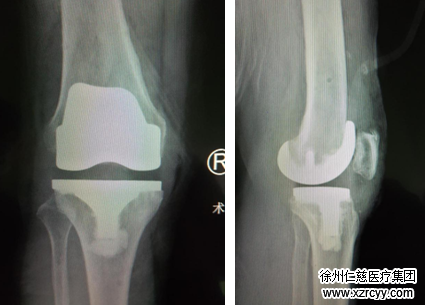

10月29日,betway在线登陆关节科再次使用引进的德国关节导航技术以及进口关节产品,为安徽宿州69岁的高老太进行了导航下右侧人工膝关节置换手术,手术经过十分顺利,术后恢复良好,目前老人正在关节病区正常康复锻炼。

在必威官方首页官网betway关节科,邱东新组长详细给老人检查后,发现老人因为病史较长,双膝关节变形较为严重,已发展为晚期的骨性关节炎,已经无法行保膝治疗了,只能行膝关节置换手术。因为右膝关节疼痛更厉害,邱东新医师决定先进行导航下的右侧人工膝关节置换术。

10月29日,邱东新组长手术团队为高老太进行了膝关节置换手术,凭借着高科技导航技术的指引,手术得以“化繁为简”,过程相当顺利,手术成功完成。术后患者假体位置良好,功能恢复十分满意。老人的罗圈腿也变直了。